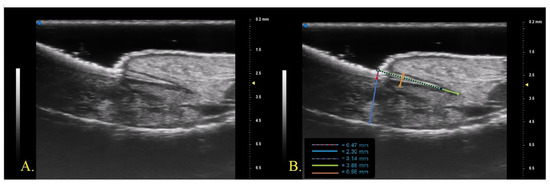

The proximal nail fold was described by studies in the literature as a structure with lower echogenicity than the ventral and dorsal plates of the nail plate [24]. In contrast, examination with a 70 MHz probe allowed precise identification of the appearance of the nail plate insertion in the distal phalanx. The dorsal and ventral plates continued beyond the cuticle as two hyperechogenic bands that converged proximally with a hypoechogenic layer in the middle. The sharpness and linearity of the US bands were higher in subjects with fewer detectable clinical changes (lower NAPSI and m-NAPSI). No data regarding the measurement of nail plate insertion length in the distal phalanx were available in the literature. The data found from our study showed that the clinical improvement detectable by a reduction in NAPSI and m-NAPSI due to treatment was associated with elongation and increased linearity of the nail plate insertion (Figure 2).

It could be hypothesized that the inflammatory state of the matrix and the periungual tissues of patients with psoriatic onychopathy caused an increase in the level of mechanical compression in the nail insertion determining qualitative and quantitative US alterations. The improvement of these parameters during the treatment with anti-IL mAbs, able to reduce the inflammatory burden, would support our hypothesis, although further studies are needed to confirm these preliminary data.

Figure 2. UHFUS (70 MHz) examination of nail apparatus, evaluated at baseline (A) and after 3 months of Ixekizumab (B).